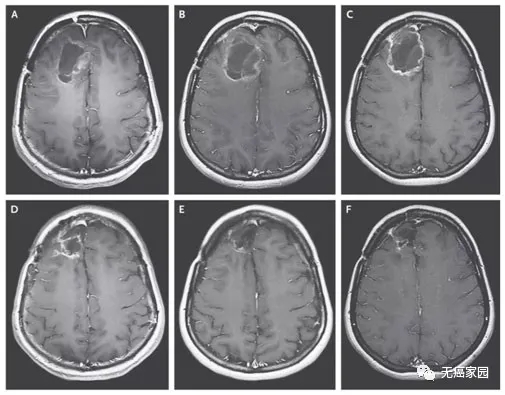

3 名患者完全缓解,他们的肿瘤在影像扫描中不再可见。12 名患者的肿瘤部分缩小,患者并未治愈,但对药物有反应的患者获得了显着的持久益处。根据一项评估,反应的中位持续时间为 13.6 个月,另一项评估为 36.9 个月。

目前所有针对胶质母细胞瘤的化学疗法的反应率都不会超过 5%,这与组合实现的 33% 的反应率形成鲜明对比。在 40 岁以下的患者中,反应率甚至更高,约为 40%。这是第一次在临床试验中证明靶向药物对胶质母细胞瘤有效,不得不说是个意外!